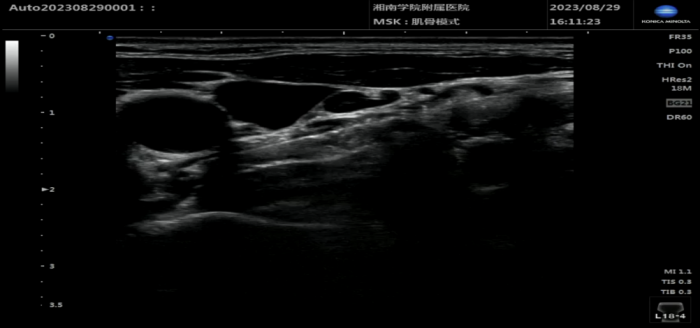

本网讯(通讯员 王珊玺)郴州市的王女士3个月前因乳腺癌术后出现左上肢肿胀、疼痛,为进一步康复治疗,来到湘南学院附属医院康复医学科求治。

由于王女士左上肢的肿胀和疼痛,已经严重影响到正常工作和生活,为此,湘南学院附属医院康复医学科主任刘松涛、王珊玺副主任医师结合患者发病经过、体格检查、康复评估、以及辅助检查结果,悉心为其设计了一套妥善的治疗方案。

“根据患者既往有乳腺手术经历,我们考虑是淋巴循环回流受阻导致手臂肿胀。”湘南学院附属医院康复医学科刘松涛主任说。医务人员为患者安排了星状神经节阻滞、针灸、特大中药封包、关节粘连传统松解术、磁疗等治疗。